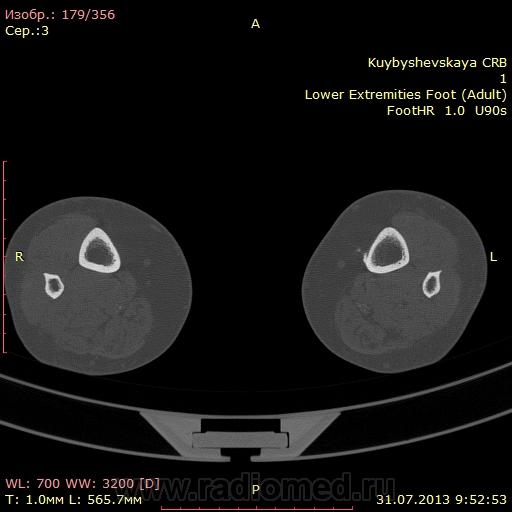

женщина. 69 лет. жалобы на боли в нижней трети голени слева в течении месяца. по снимкам врач написал периостит(к сожалению фотоаппарата нет под рукой)В ближайшее время травм не было. мне досталась только карточка. Пациента не видел. Помогите с диагностикой. вроде бы на зло не похоже. или ошибаюсь?

На зло непохоже, нет мягкоткотканного компонета. Передне-медиальная поверхность голени - самое место для травмы. Только термин "периостит" мне тоже не нравится, написал бы - локальное обызвествления мягких тканей, вероятнее всего посттравматического характера.

По снимкам описал бы как обызвествившуюся гематому, а по КТ больше тянет на экзостоз, только основание очень широкое.

Тем более не "зло". На боковом снимке, в захваченной стопе, р-признаки синдрома переднего большеберцово-таранного соударения. Она же стопа "футболиста" или спортсмена

Может "...в ближайшее время травм И не было...", но что его, наверняка, когда-то "подковывали" бутсой по передней поверхности голени, несомненно.